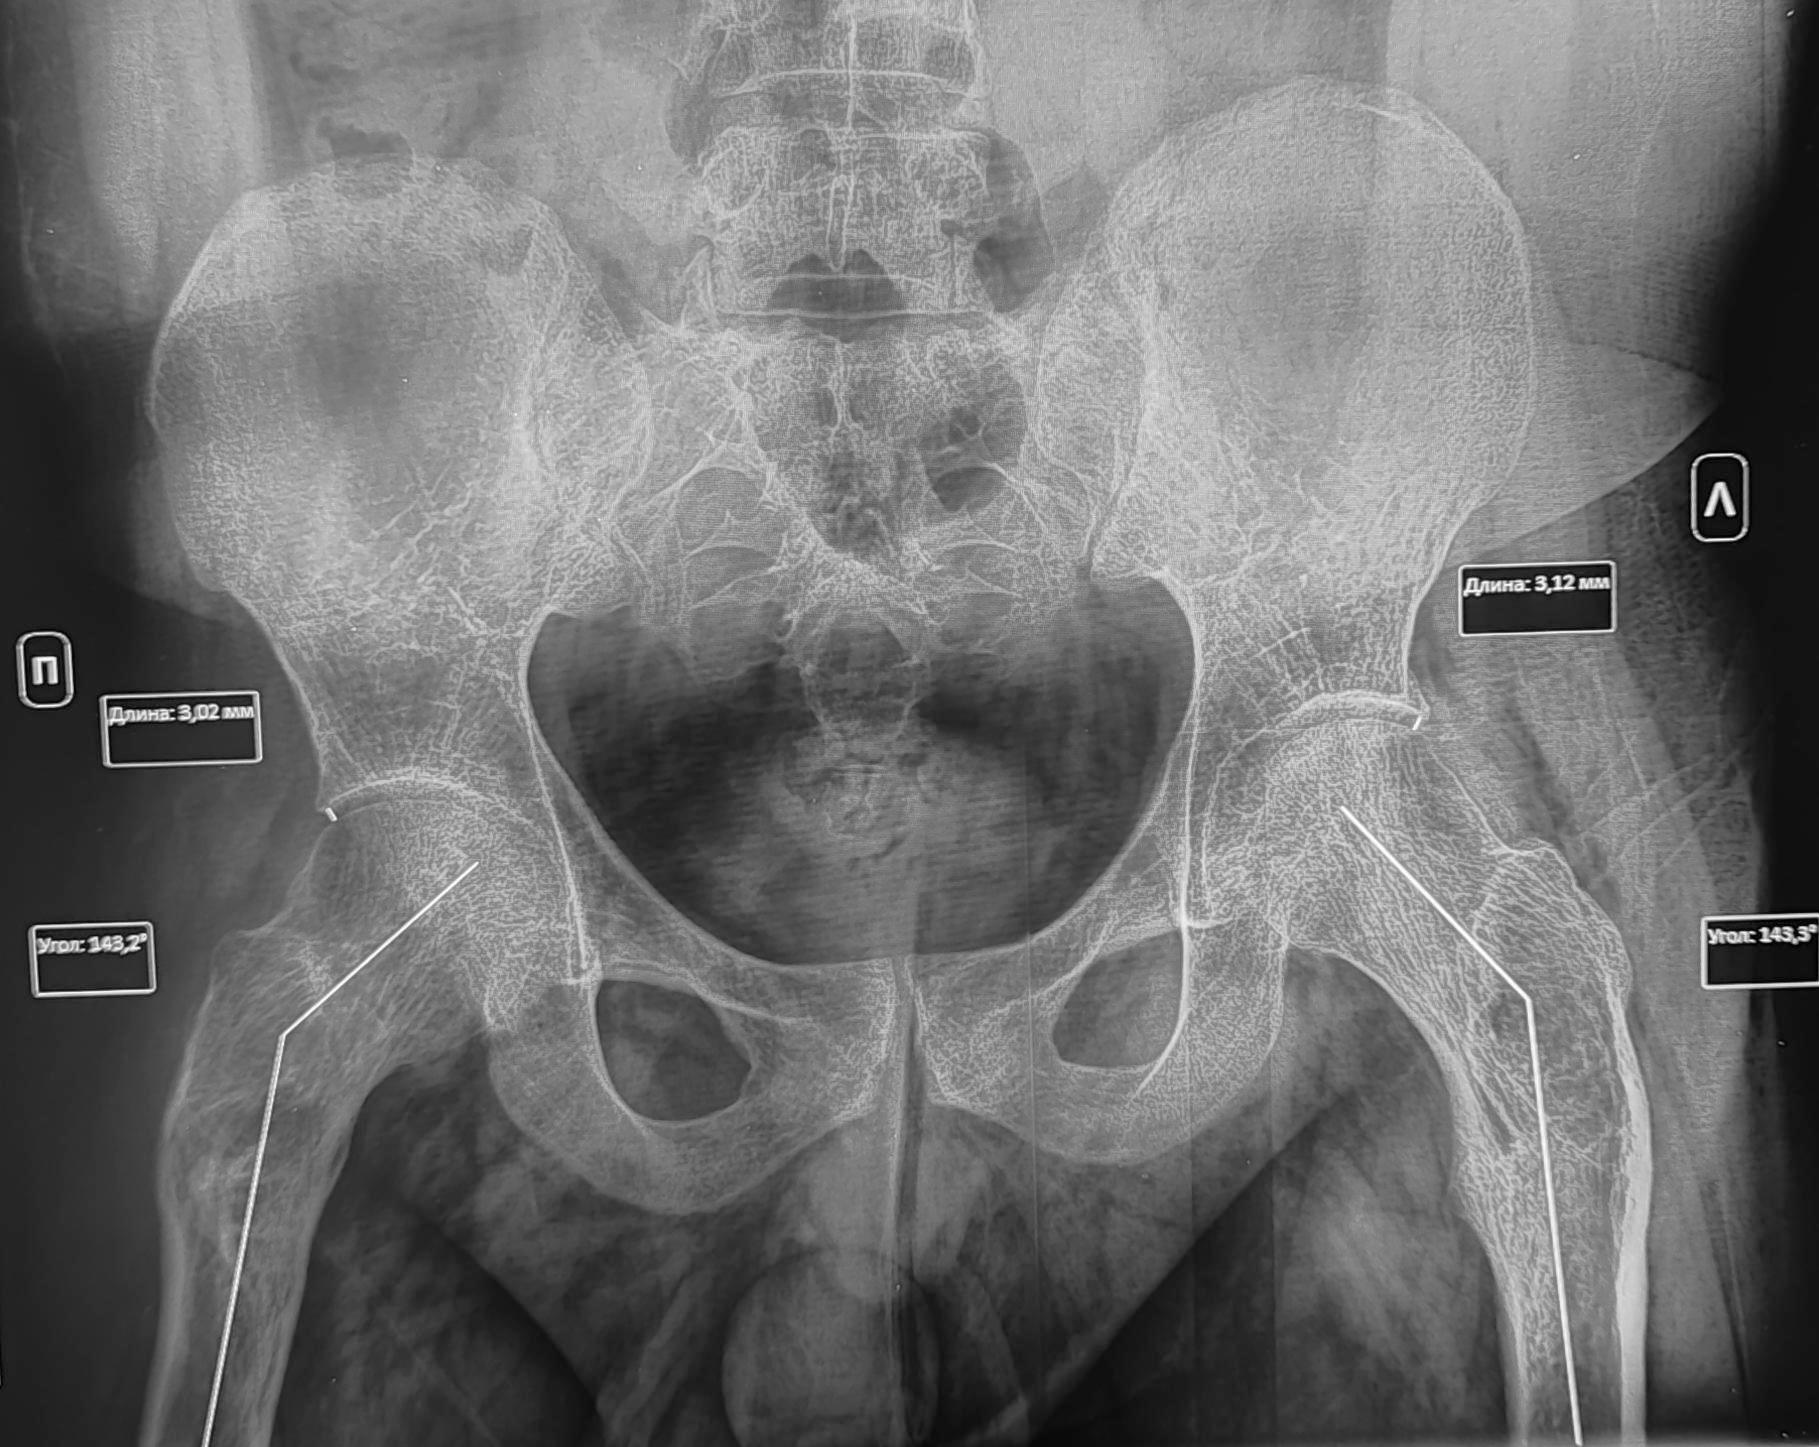

В анамнезе у призывника диагноз- дисплазия тазобедренных суставов, перенесенное оперативное лечение по поводу дисплазии в детстве. По данным рентгенографии костей таза: ШДУ справа 143 град, слева 143 град, сужение суставной щели справа до 3 мм, слева до 3.1 мм, остеофиты по верхне-наружным краям суставных щелей, шейка правой бедренной кости укорочена ,перекос таза вправо. Двусторонние участки разряжения костной ткани в межвертельной области(более выраженно справа)-как следствие перенесенных оперативных вмешательств. Заключение: Coxa valga bilateralis как следствие дисплазии тазобедренных суставов. Вторичный двусторонний коксартроз 1ст.